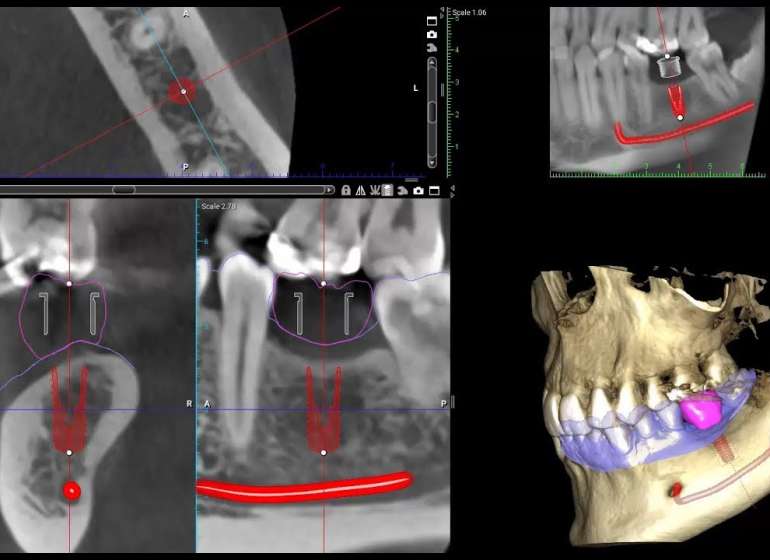

3D KT yüksək dəqiqliyə malik rəqəmsal diaqnostika üsuludur ki, onun sayəsində diş-çənə sisteminin və sinus ciblərinin üçölçülü görüntüsünü əldə etmək mümkündür. 3D KT-nın köməyi ilə sümüklərdə, dişlərdə və yumşaq toxumalarda adi 2D Panoram rentgenoqrafiyalarda görünməyən dəyişiklikləri aşkar etmək olur. Müasir 3D KT diaqnostikası sadə, tez və ağrısız bir prosedurdur.

• Diş köklərinin, kanallarının strukturunu qiymətləndirmək;

• Dişlərin keyfiyyətli mülaicəsi üçün kanalların dəqiq sayını və strukturunu müəyyən etmək;

• Retenləşmiş dişlərin çənə sümüyündə istiqamətini (3 boylu görüntüsü) görmək;